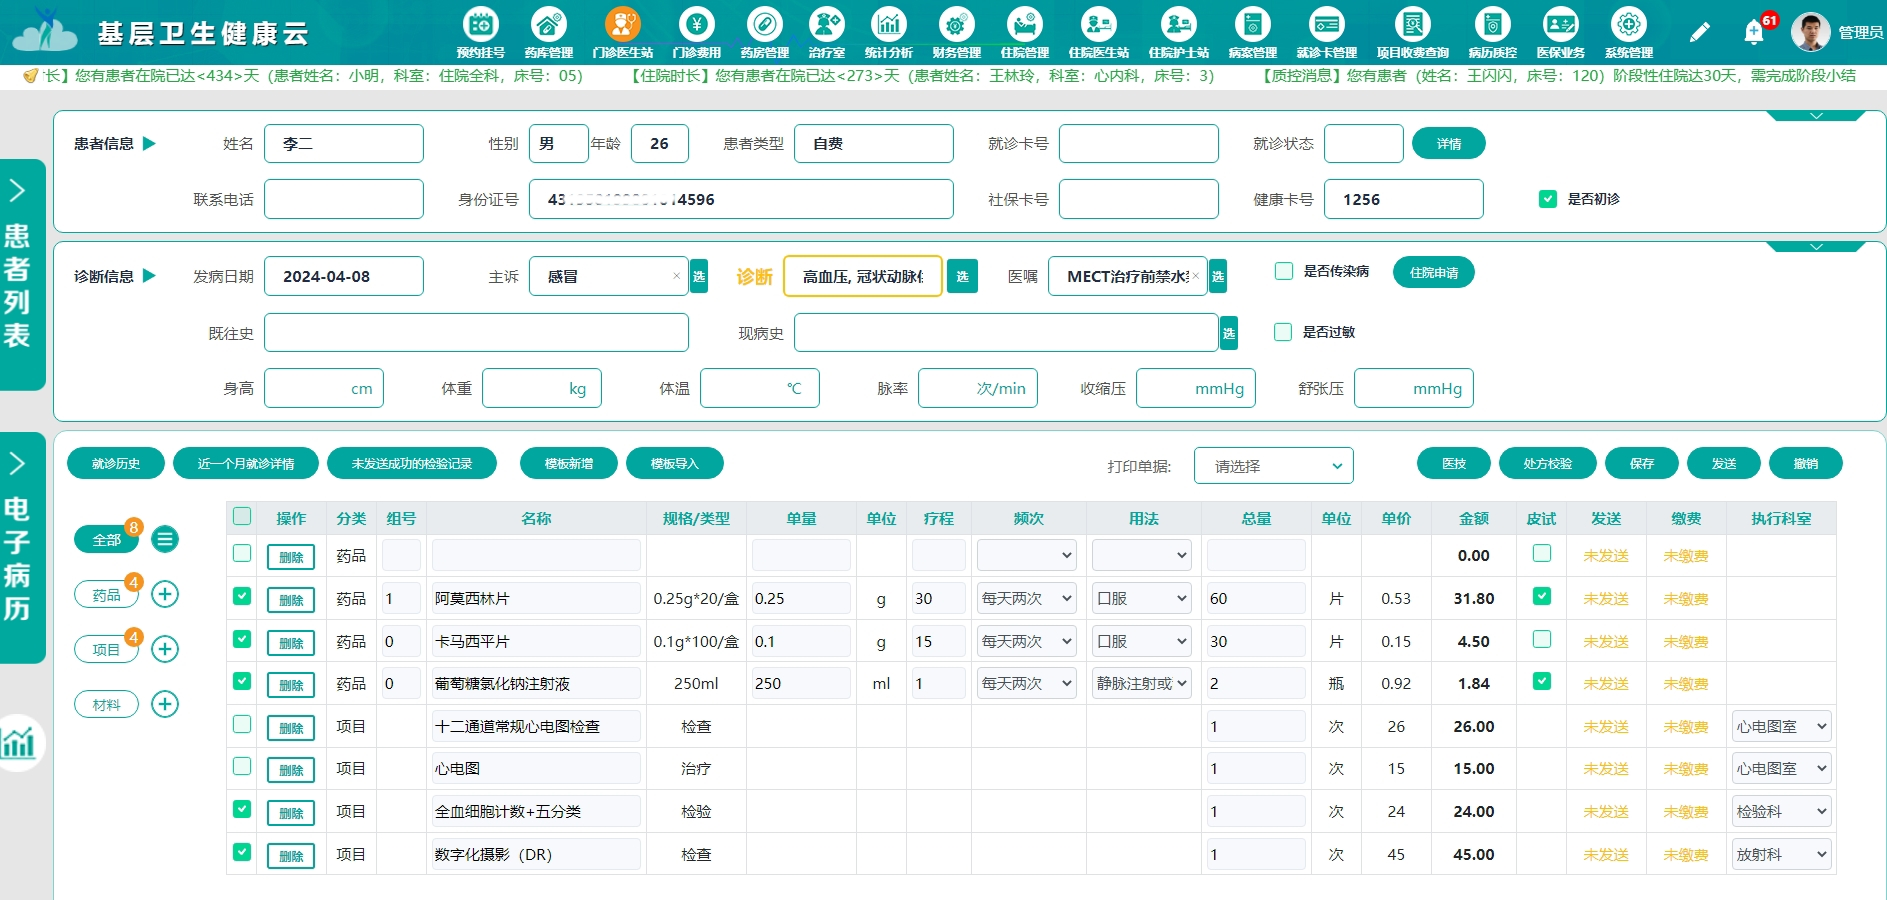

一、SaaS模式Java语言开发的云HIS系统

在公立二甲医院应用多年,融合B/S版电子病历系统,支持电子病历四级,云HIS系统支持病患预约挂号支持、病患问诊、划价收费、电子病历、开药发药、住院出院、会员管理、统计查询、医生工作站和护士工作站等一系列常规功能,能与公卫、PACS等各类外部系统融合,实现多层机构之间的融合管理。